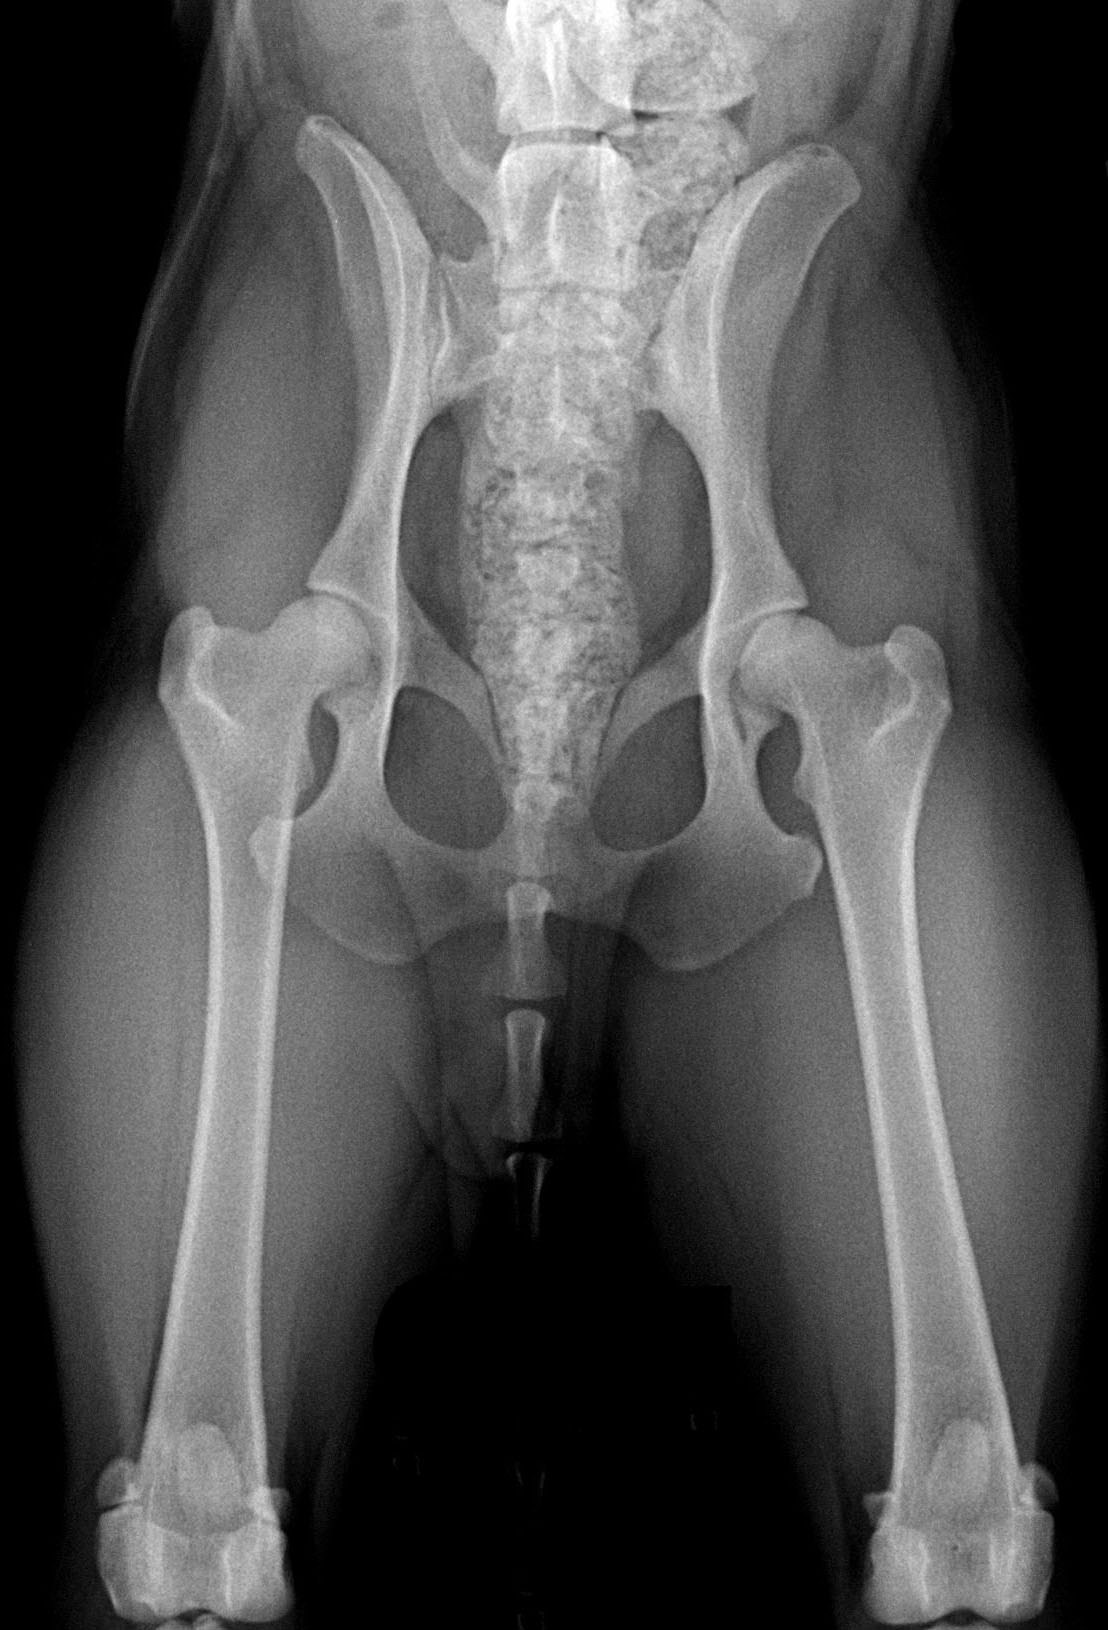

ДТБС у собак: рентгенограммы

ДТБС: степень "С" — начальная форма